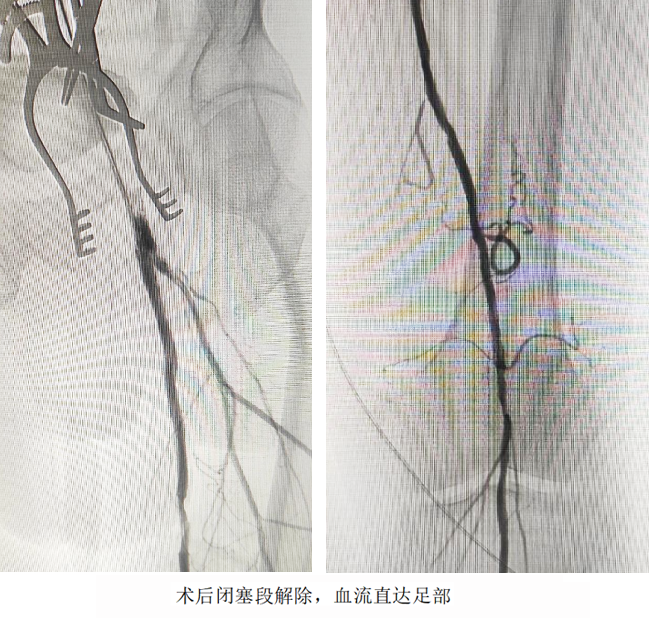

開放手術精準“拆彈”,切開股動脈,直視下完整剝脫致密鈣化斑塊,重建股總動脈血流通道;介入技術微創“護航”,經血管腔植入髂動脈覆膜支架,快速隔絕夾層破口,防止主動脈進一步撕裂;利用長球囊對股淺動脈閉塞段進行“拓荒式”擴張,并植入柔性支架重塑血管,確保血流直達足部。

術后次日,患者左下肢皮溫回升,疼痛消失;術后第3天,患者已實現獨立行走。家屬感激地說:“本來以為要坐輪椅了,沒想到還能重新站起來!”